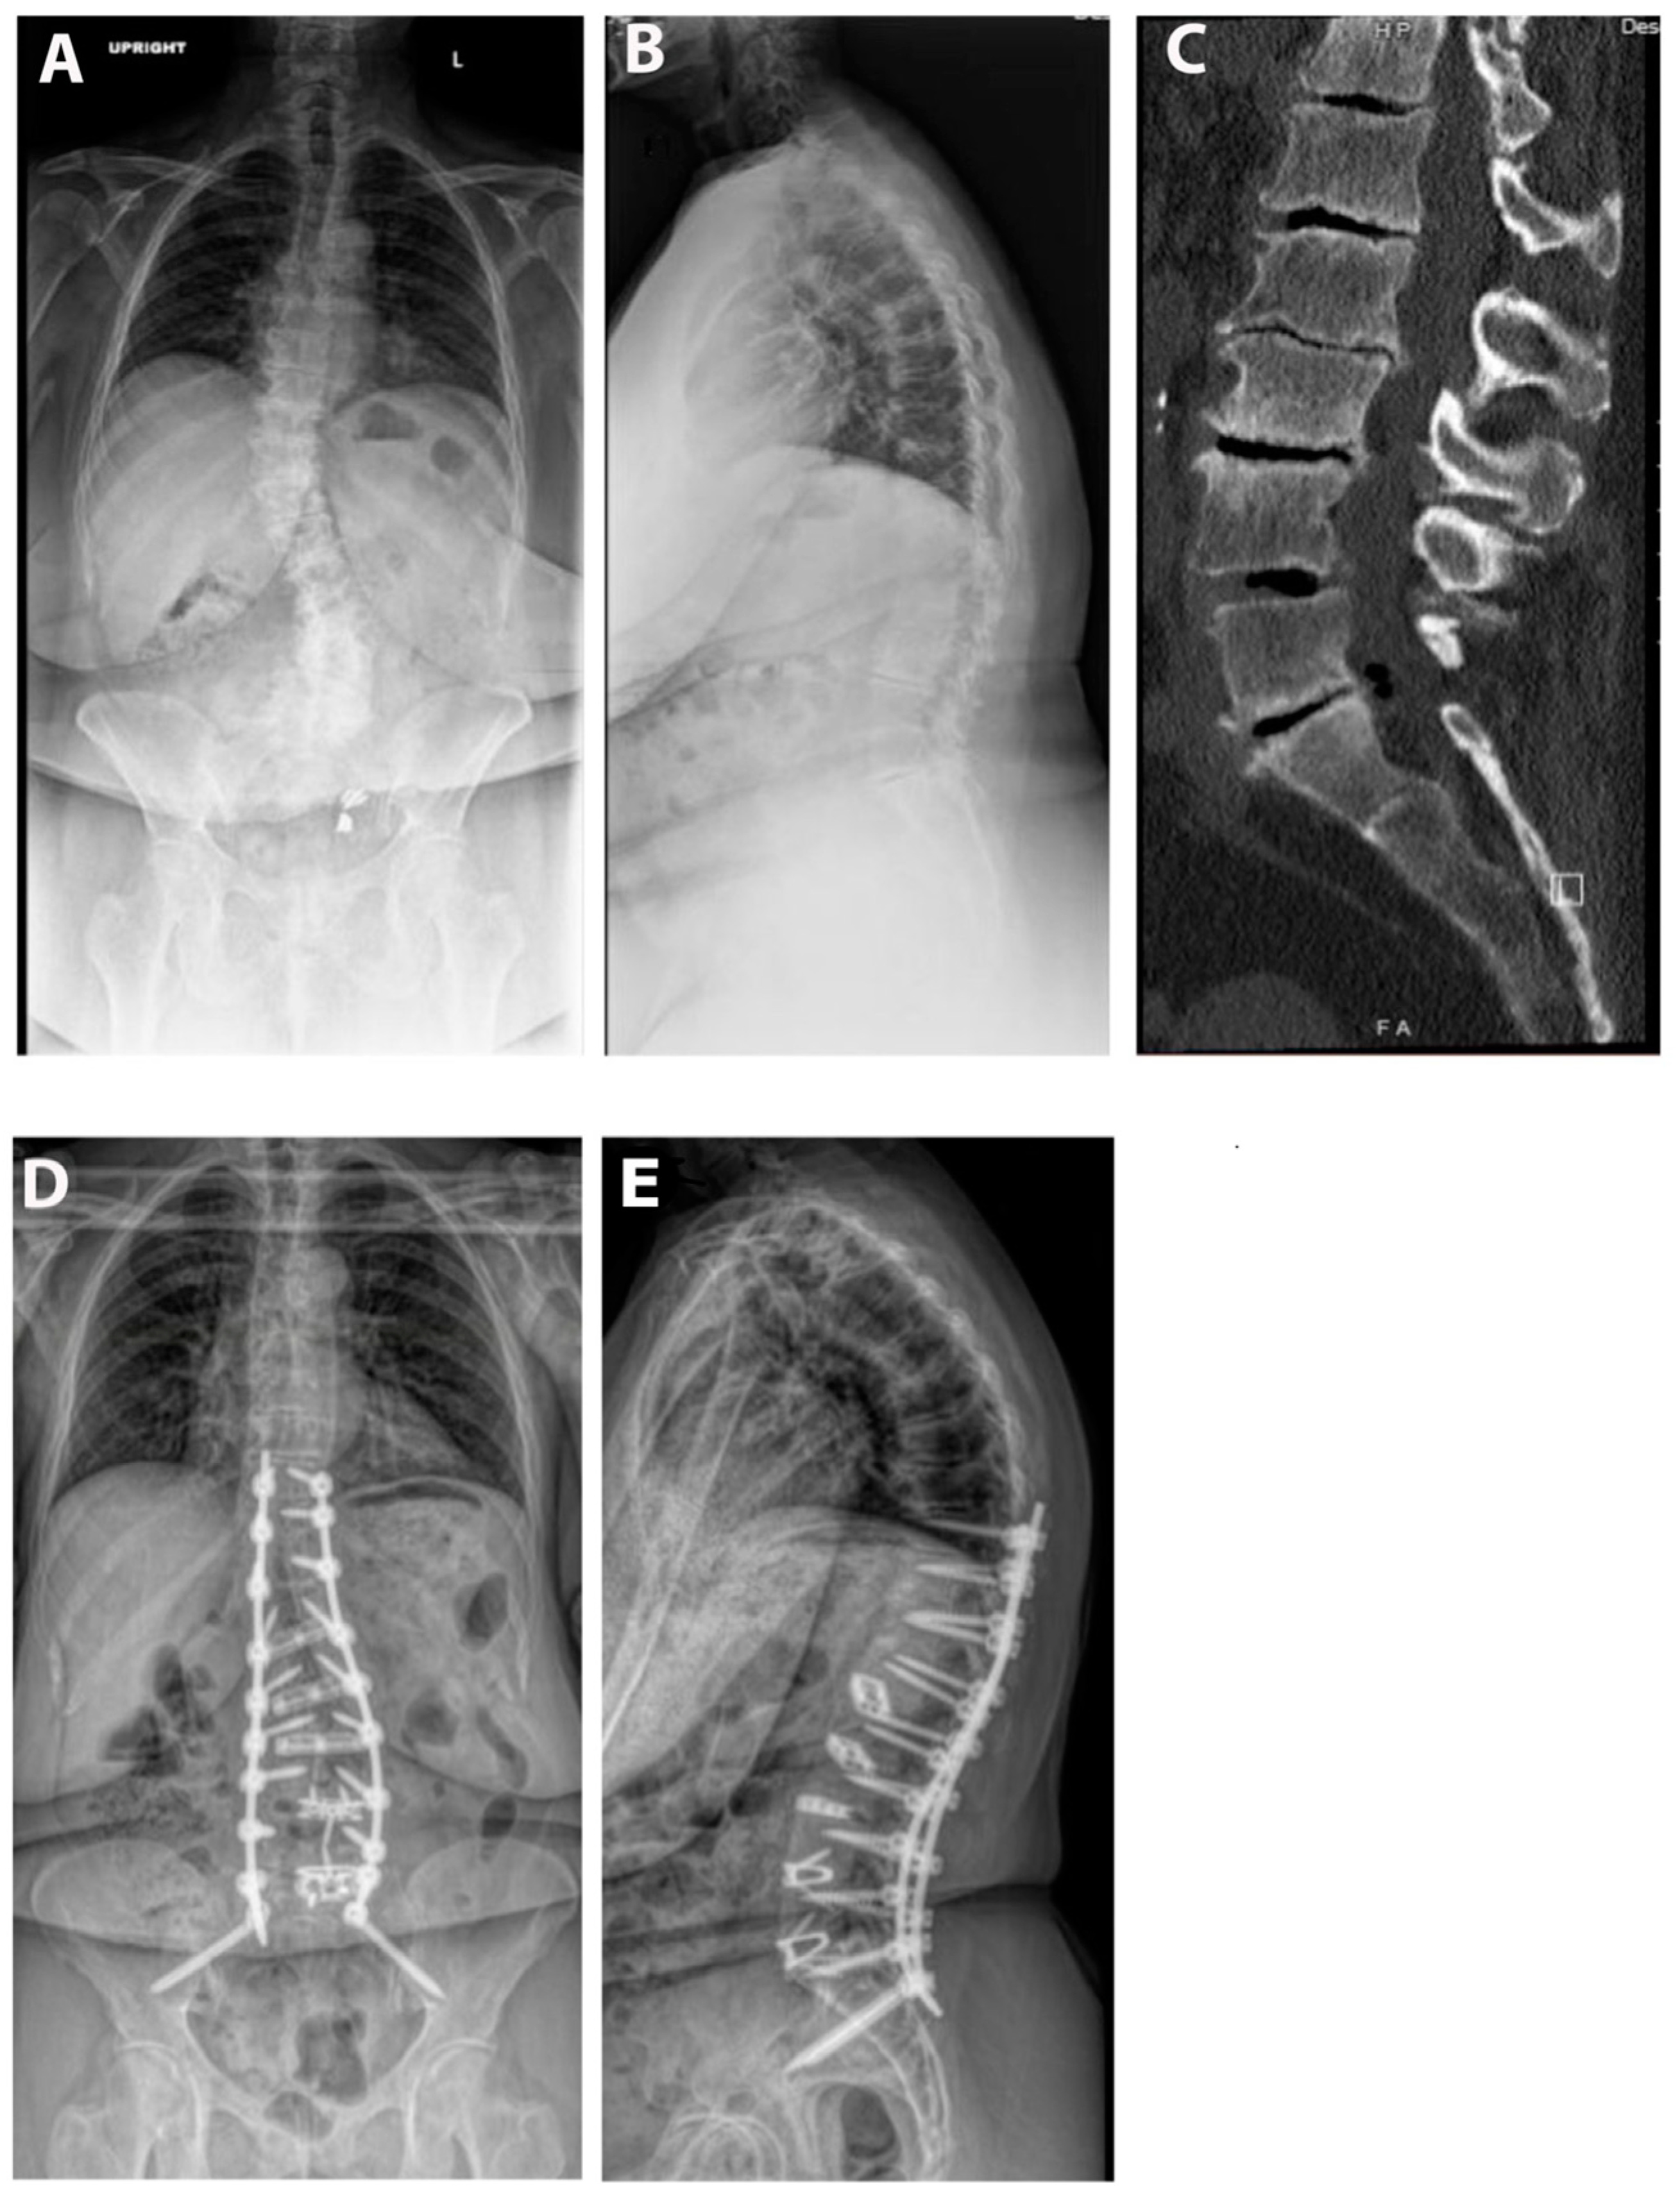

Pre- and postoperative measurements were made of spinopelvic parameters from full-length standing X-rays (Figure 2 and Table 3). Postoperative measurements were taken at the last follow-up appointment. These patients had a mean SVA pre-operatively of 11.8 (range: 5.5 to 23), and on average improved by 2.4 cm (range: −0.7 to −4.7, p = 0.15). Mean pre-op PI-LL mismatch was 27.1 (range: 11 to 42) and this decreased significantly by 7.9° (range: 5 to 32, p = 0.01). Lumbar lordosis (LL) increased significantly, on average by 9.1° (range: −2 to 31, p = 0.01) after surgery, and the mean change in pelvic tilt (PT) was 3.3° (range: −13 to 4, p = 0.04). The mean coronal Cobb angle was 12.9° preoperatively (range: 1 to 36), with a significant mean postoperative decrease of 6.3° (p = 0.03). The average change in segmental SL was +12.2° (range: +4 to +23, p = 0.004). On average we placed 10.63° (range: 10–15) of cages in these patients (Figure 3). Of note, only one patient had a posterior column osteotomy. An example case of a patient who underwent an L5-S1 ALIF with L2-5 prone lateral interbody fusion is shown in Figure 4.

Figure 4.

Example case. The patient is a 67-year-old male with a BMI of 36. He was having severe back and leg pain and had attempted extensive conservative measures. His pre-op SVA was 11 and PI-LL mismatch was 35°. He underwent an L4-S1 ALIF and then a L2-5 prone lateral with T10-pelvis posterior fusion. (A) Pre-op upright AP X-ray. (B) Pre-operative upright lateral X-ray. (C) Pre-operative CT scan. (D) AP postoperative upright AP X-ray. (E) Postoperative upright lateral X-ray.